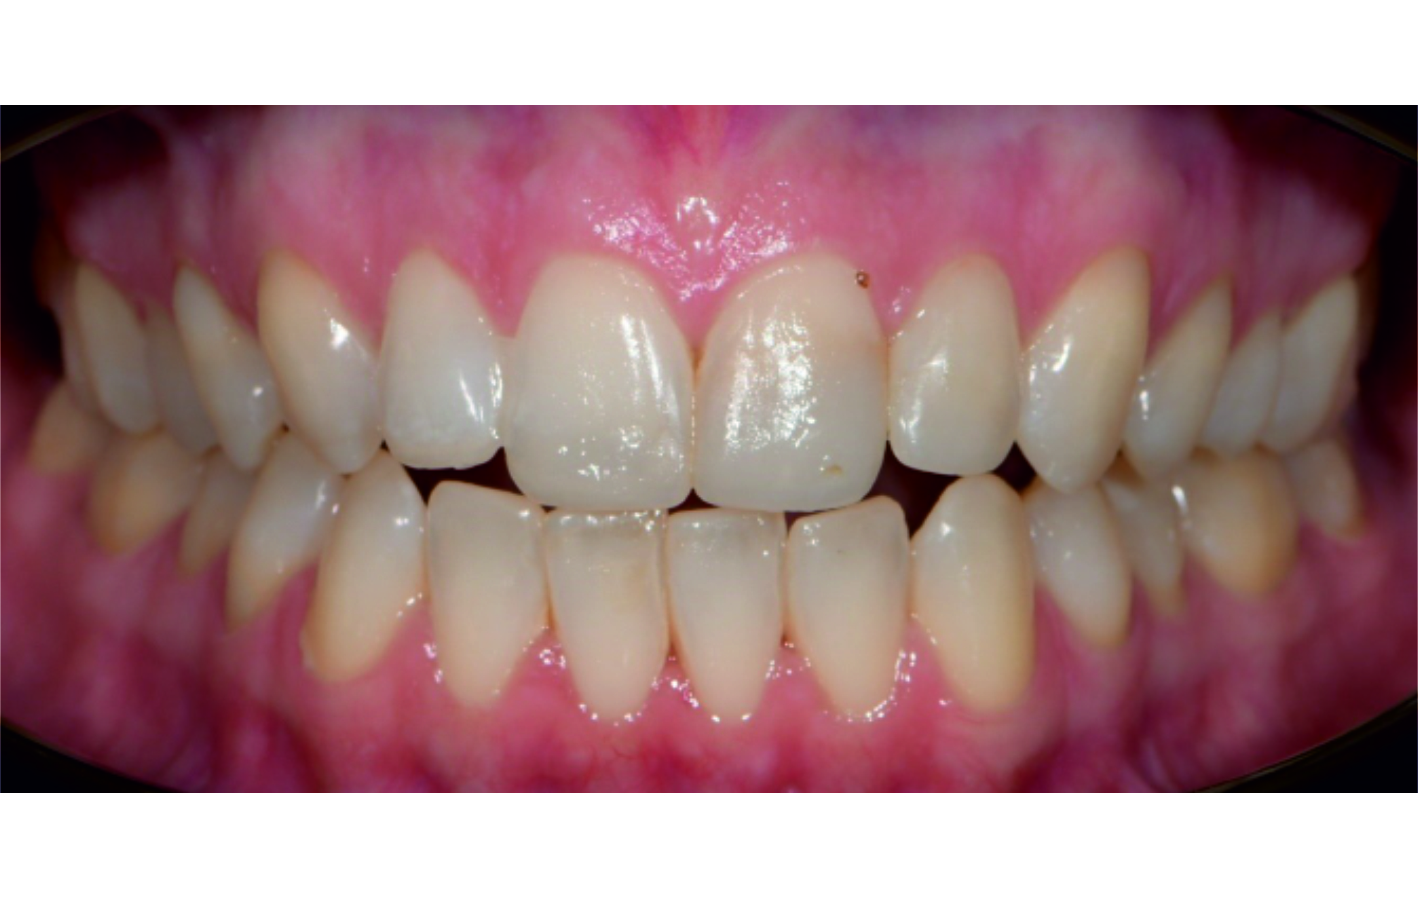

Angel Aligner PRO: Correction of a class II div 1 malocclusion

By Dr. Dalia Latkauskiene

This case, led by Dr. Dalia Latkauskiene, presents the treatment of a 25-year-old female patient with a Class II division 1 malocclusion. Using the Angel Aligner PRO system with dual-modality mechanics, the treatment achieved derotation of molars, midline correction, open-bite closure, and Class I settling. In just 12 months and 40 aligners, the approach delivered precise control, enhanced function, and a significantly improved smile.